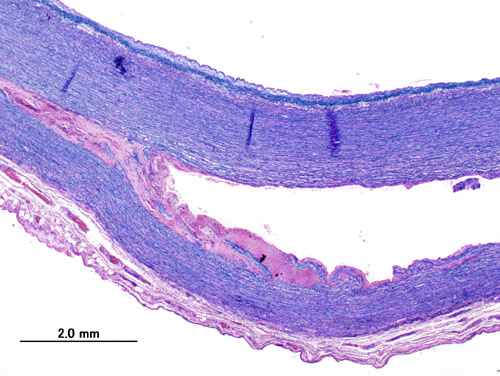

Histologically, atherosclerosis consists of a fibromuscular cap covering a necrotic lipid core (mainly cholesterol).

Hyperplastic arteriolosclerosis thickens the artery wall by causing smooth muscle hyperplasia in an “onion-skin” pattern.

Fibrinoid necrosis of the vessel wall may also be seen in hyperplastic arteriolosclerosis.

Mönckeberg medial calcific sclerosis results in the calcification of the muscular tunica media portion of medium-sized arteries.

Weakness of the connective tissue in the media is a characteristic symptom of Marfan syndrome and Ehlers-Danlos syndrome (cystic medial necrosis).

Tertiary syphilis results in the aorta having a “tree-bark” look.